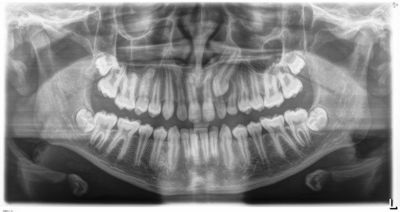

One case posted to the community involved a 13-year-old with a lingually displaced UL3 and plans for full braces, extraction of the primary ULc, and possible exposure and ligation (Figs. 1–5). The treating orthodontist asked: How likely is this canine to correct on its own after extraction?

Fig. 3